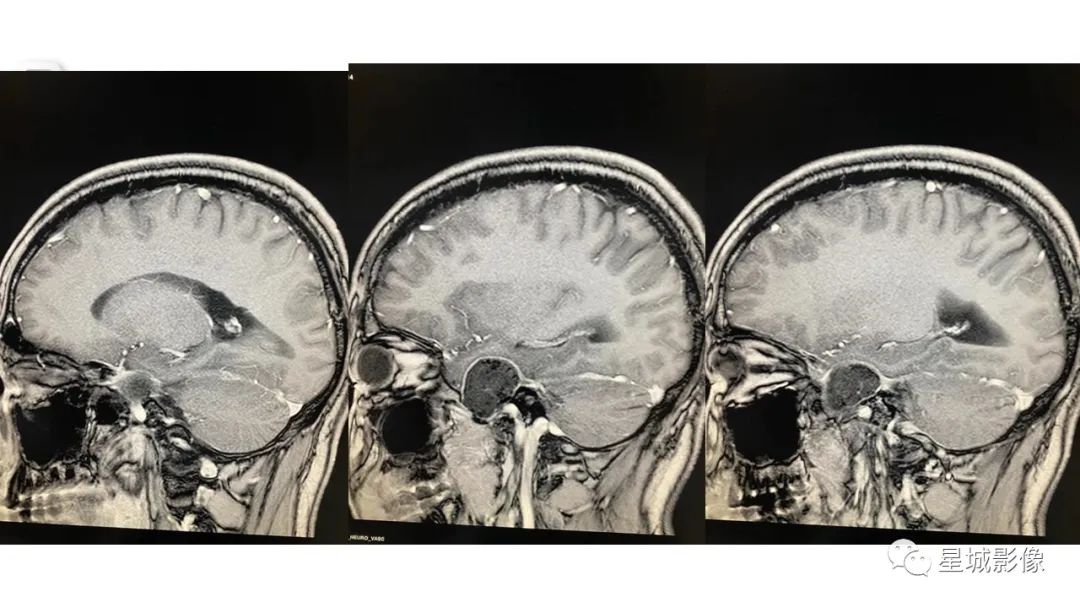

【病例】颅内成熟性囊性畸胎瘤1例MR影像表现-7

【病例】颅内成熟性囊性畸胎瘤1例MR影像表现-8

【病例】颅内成熟性囊性畸胎瘤1例MR影像表现-9